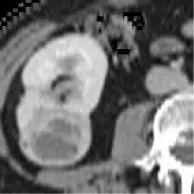

Patients with a pathological diagnosis obtained by biopsy or surgical resection were included in this study. In addition, 80 patients with available arterial/cortical/nephrogenic phase CT image sequences were reviewed (42 with PRCC and 38 with ChRCC). After randomly selecting 6 cases (3 PRCCs and 3 ChRCCs) for testing sets, the images of 74 tumors (39 PRCCs and 35 ChRCCs) were used to build the datasets. The CT images were obtained using various radiology scanners and non-standard protocols. Arterial phase sequences were preferred when multiple phases existed. Whole sequences were retrieved and exported utilizing the hospital radiological database. The window settings were 40 HU (width) and 400 HU (level). Based on the clinical and pathological data, ROIs of sequences were segmented, labeled, and exported with ITK-SNAP by two abdominal radiologists who have experience of more than 10 years in the diagnosis of urinary system tumor. After cross-validation, images that were exported in.jpg size included 857 images of ChRCCs and 997 images of PRCCs. Labeling was applied in the non-graphical layer so that each slice filename contained the case number, gender, age, and histological subtypes. After resizing, images comprised matrices with 256 * 256 pixels in the axial planes. The dataset was divided into the training set and validation set (90% for the training set and 10% for the validation set).